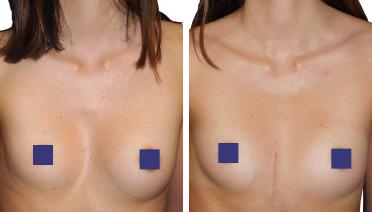

La tecnica di impianto su misura è una tecnica chirurgica minore che consiste nel riempire la concavità creata dal Pectus con un impianto personalizzato. Si tratta di un intervento rapido, a basso rischio, con un risultato immediato e una breve convalescenza.

In questa pagina, troverà i risultati di questa operazione a seconda del tipo di Pectus : mediale, asimmetrico, più o meno profondo o lungo.

Tipo 4 : Pectus Arcuatum,